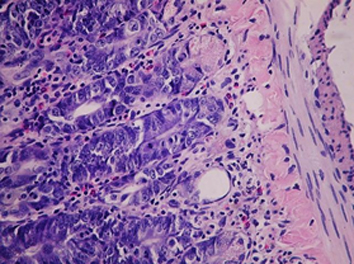

Результаты. Показано, что применение рифабутина в сочетании с аскорбигеном приводит к ослаблению повреждающего действия антибиотика на слизистую оболочку желудочно-кишечного тракта и ускорению процессов восстановления ее структуры, что клинически выражается в нормализации прироста массы тела животных. При комбинированном применении рифабутина с аскорбигеном уменьшается глубина цитопении, а количество лейкоцитов в периферической крови крыс восстанавливается быстрее. Признаки атрофии лимфоидной ткани селезенки отсутствуют. Введение аскорбигена до рифабутина оказывает протекторный эффект в отношении тканей почек и семенников.